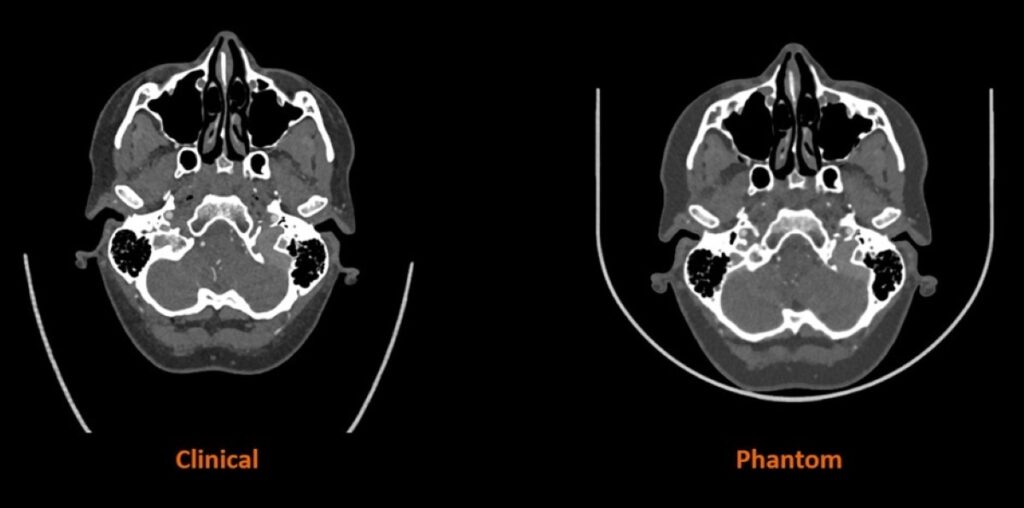

Het geavanceerde algoritme van Siemens Healthineers vertaalt de gescande patiëntbeelden naar specifieke materiaaleigenschappen met radiopaciteit van de menselijke anatomie. Zo 3D print men op maat gemaakte fantomen met ultra realistische menselijke anatomiekenmerken iets wat tot nog toe niet mogelijk is. Beginnend met de productie van 3D-geprinte fantomen voor kleinschaligere anatomieën van het hoofd-halsgebied, zal het onderzoek de productie van steeds grotere en complexere anatomieën omvatten. Het eindpunt wordt het 3D-printen van een hartmodel en van een volledige menselijke romp met volledige radiografische nauwkeurigheid.